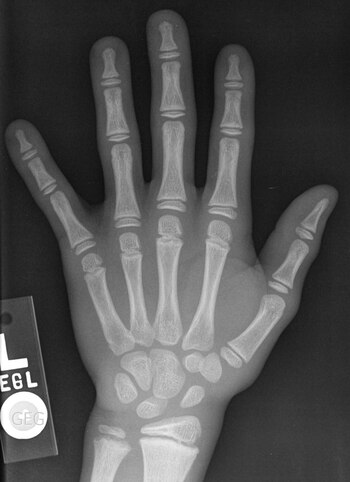

Quizá recuerde algún momento de la infancia en el que vio los huesos de su mano sobre un fondo oscuro. ¿Cómo era posible fotografiar algo que se escondía bajo la piel? ¿Qué tipo de truco usaba aquella persona que huía al otro lado del cristal durante un puñado de segundos?

La invención de la radiografía se la debemos al alemán Wilhelm Röntgen, quien a finales del s. XIX descubrió un nuevo tipo de rayos capaces de atravesar ciertos materiales. Como su naturaleza era desconocida, los llamó rayos X. Experimento va, experimento viene, observó que esa radiación podía atravesar el tejido humano con más facilidad que los huesos. Así logró la primera radiografía médica de la historia, la de la mano de su mujer, Bertha.

Ha pasado más de un siglo desde aquel momento y, pese a que se han realizado numerosos avances, el fundamento sigue siendo básicamente el mismo. Para comenzar se necesita una fuente que emita rayos X, un tipo de radiación de la misma naturaleza que la luz visible, pero más energética y con mayor capacidad de penetración.

Los rayos X atraviesan en mayor o menor medida el objeto que se ponga en su camino y llegan a una placa fotográfica. Esta placa está formada por ciertos compuestos químicos (haluros de plata) que, al entrar en contacto con los rayos X, se oscurecen. Por lo tanto, cuantos más rayos X incidan sobre una zona, más se oscurecerá ésta.

Dado que los rayos X atraviesan con más facilidad los materiales con átomos más ligeros, como los que hay en la piel y los músculos, estas partes del cuerpo se verán más oscuras en la radiografía. Todo lo contrario pasa con los huesos que, al estar formados por átomos más pesados, aparecen más blancos. Obviamente, el grado en el que se oscurece la placa también depende de la densidad o el grosor del objeto: cuanto mayor sea, menos rayos conseguirán atravesarlo y más clara será la radiografía.